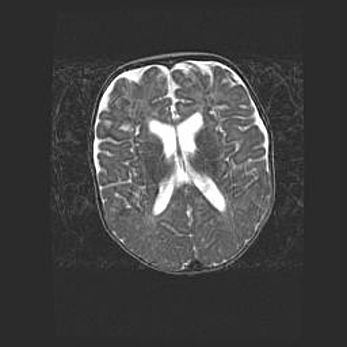

Сообщающаяся гидроцефалия. Кистозная энцефаломаляция головного мозга.

Возраст: 3 месяца 4 дня

Вес: 3100 г

Пол: женский

Окружность головы: 34 см

Срок гестации: 31 неделя

Кистозная энцефаломаляция головного мозга - одна из форм поражения головного мозга в детском возрасте. Характеризуется возникновением множественных и распространённых кист в коре, белом веществе и подкорковых образованиях головного мозга у плодов, новорождённых и детей раннего возраста. Развитие кистозной энцефаломаляции связано с внутриутробной асфиксией и гипотонией, родовой травмой, тромбозом синусов, пороками развития сосудов, инфекциями, сепсисом и другими причинами. Наиболее значимые инфекционные агенты: вирусы простого герпеса, цитомегалии, краснухи, токсоплазмы, энтеробактерии, золотистый стафилококк и другие.